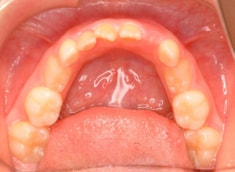

治療後(1年5ヶ月後)

治療開始から11ヶ月